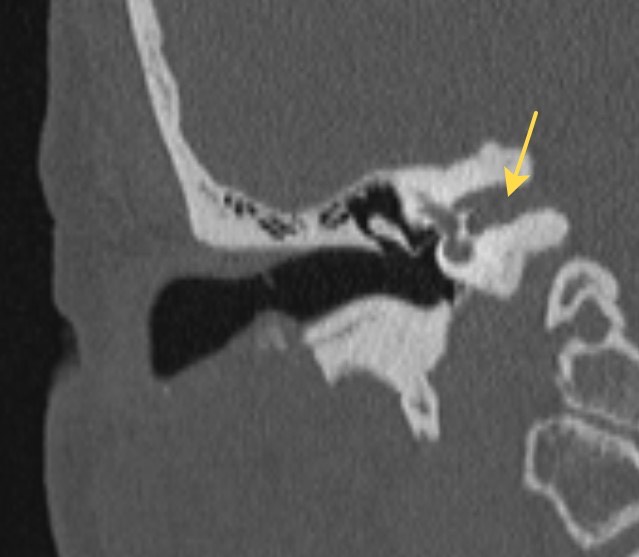

2429. Анатомическая структура, отмеченная на снимке, является